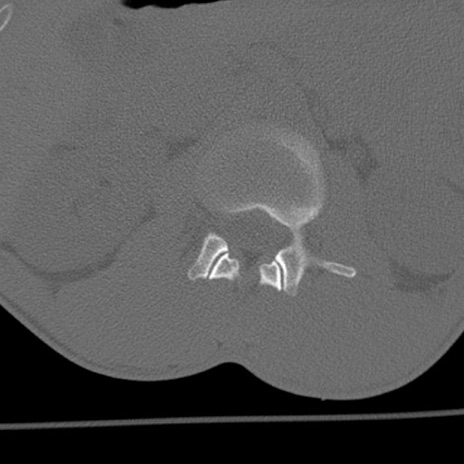

症例3 腰椎CT(横断像)

腰椎CT